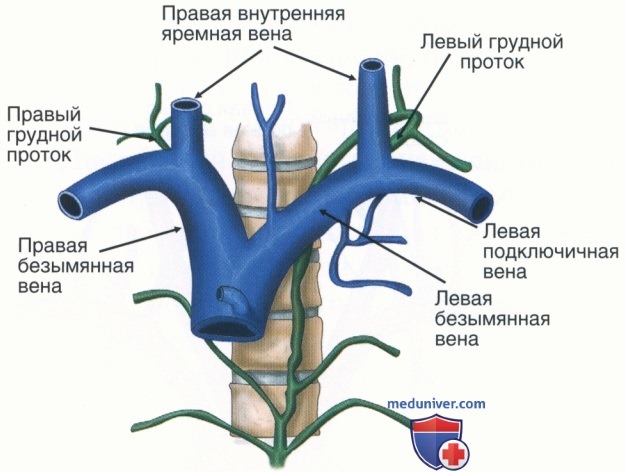

Анатомия внутренней яремной вены: КТ изображения